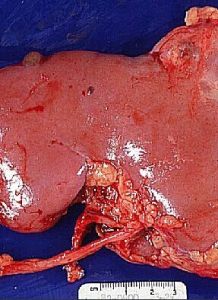

(2)下腔靜脈癌栓:腎癌容易發生腎靜脈和下腔靜脈內癌栓,近年來認為,如未發現局部或遠處擴散,腎癌根治切除術時可同時切除靜脈內癌栓或取出下腔靜脈內癌栓,預後仍然良好。手術時阻斷下腔靜脈應在血栓水平以上,可避免致命的肺栓塞。如血栓延伸到心臟,可在心包內把下腔靜脈阻斷,再切開下腔靜脈,取出栓子。